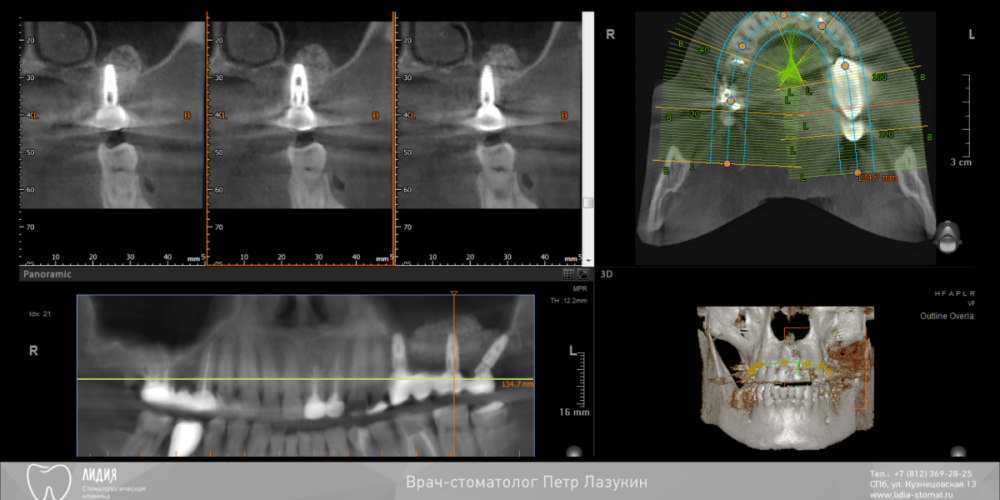

pit Опубликовано 22 декабря, 2021 Поделиться Опубликовано 22 декабря, 2021 Всем привет! Клинический случай. Реферативный пациент. В анамнезе несостоятельная костная пластика и несостоятельный синус-лифтинг (или даже два). Выбрана тактика: имплантация в позиции 25 27 28 (под углом 45 градусов) одномоментно с ОСЛ. В случае очередной неудачи протезирование было бы выполнено протезирование компромиссной конструкцией с опорой на 25 28 импланты. Во время операции произошел полный разрыв слизистой пазухи. Палатинальная стенка была скелетирована и к ней подшита мембрана с формированием купола. Уложен графт ИНТЕРОС, установлены импланты Хай-Тек. Швы. Протезирование МК коронками с винтовой фиксацией с уровня МЮ и платформ через 12 месяцев 13 1 2 Ссылка на комментарий